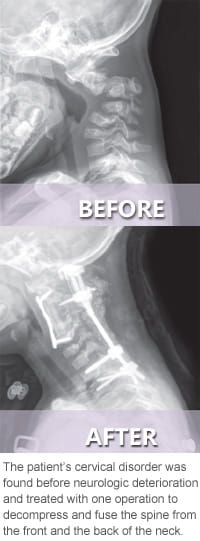

The Cervical Spine Clinic at Cincinnati Children’s is for children and teens with rare and complex cervical spine conditions. When you come here for care, you’ll benefit from highly skilled specialists, innovative surgical techniques and the latest technology.

The Cervical Spine Clinic team cares for children with spine conditions related to syndromes. We have experience treating both common and complex syndromic disorders, including: